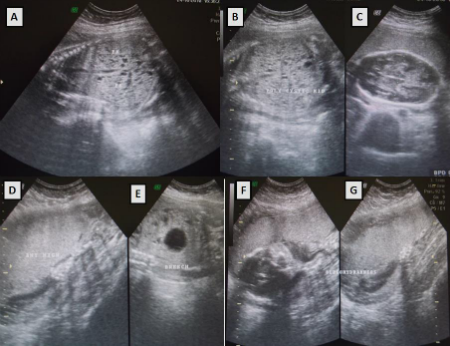

A 25-year-old pregnant female reported at 28 weeks of gestation with non specific abdominal pain. On evaluation, the ultra-sonogram revealed a single live fetus in breech presentation. Placenta was anterior and high and there was severe oligohydramnios. Both fetal kidneys were enlarged in size (occupying most of the abdominal cavity) and homogenously hyperechoic & studded with numerous variable sized cysts. Besides, cisterna magna was also prominent. There was no other significant past medical or surgical history and she had delivered one healthy male child before three years. Both spouses were normal on clinical evaluation and there was no family history of renal diseases on the either side. Ultrasonogram ruled out any features of renal diseases in both spouses and the first child. The diagnosis of autosomal recessive polycystic kidney disease (ARPKD) was made on the basis of fetal imaging and absence of any family history of renal disorders. The pregnancy delivered vaginally at 32 weeks of gestation. The baby had severe respiratory distress and died within the first few hours of life. No pathological post-mortem or DNA analysis was possible due to logistic issues.

Figure 1: High resolution fetal ultrasonogram depicting (A , B, C) Hyperechoic and enlarged kidneys characteristic of in autosomal recessive polycystic kidney disease; (D) High, anterior placenta; (E) Breech presentation; (F, G)Oligohydramnios |